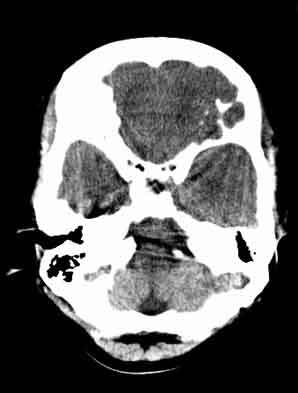

患者,女,29,头痛呕吐2月余,已建议增强或mri进检。

额叶脑白质象是有问题

额叶低密度影,建议增强。

脑沟裂消失,脑白质密度似有减低,考虑脑炎。

左额叶白质密度减低,考虑脑炎,建议增强或mri .

大脑表面脑沟裂消失,颅压高的表现,经常遇到这样的现象,都没有一个明确的结论,望高人指点。

额叶密度减低好像伪影。

左侧额叶见低密度影,边界模湖 建议 增强 除外占位

双侧脑室前角、旁周围白质低密度减低,边界模糊不清,患者女性:大胆推测,脑白质脱髓鞘改变。mri检查